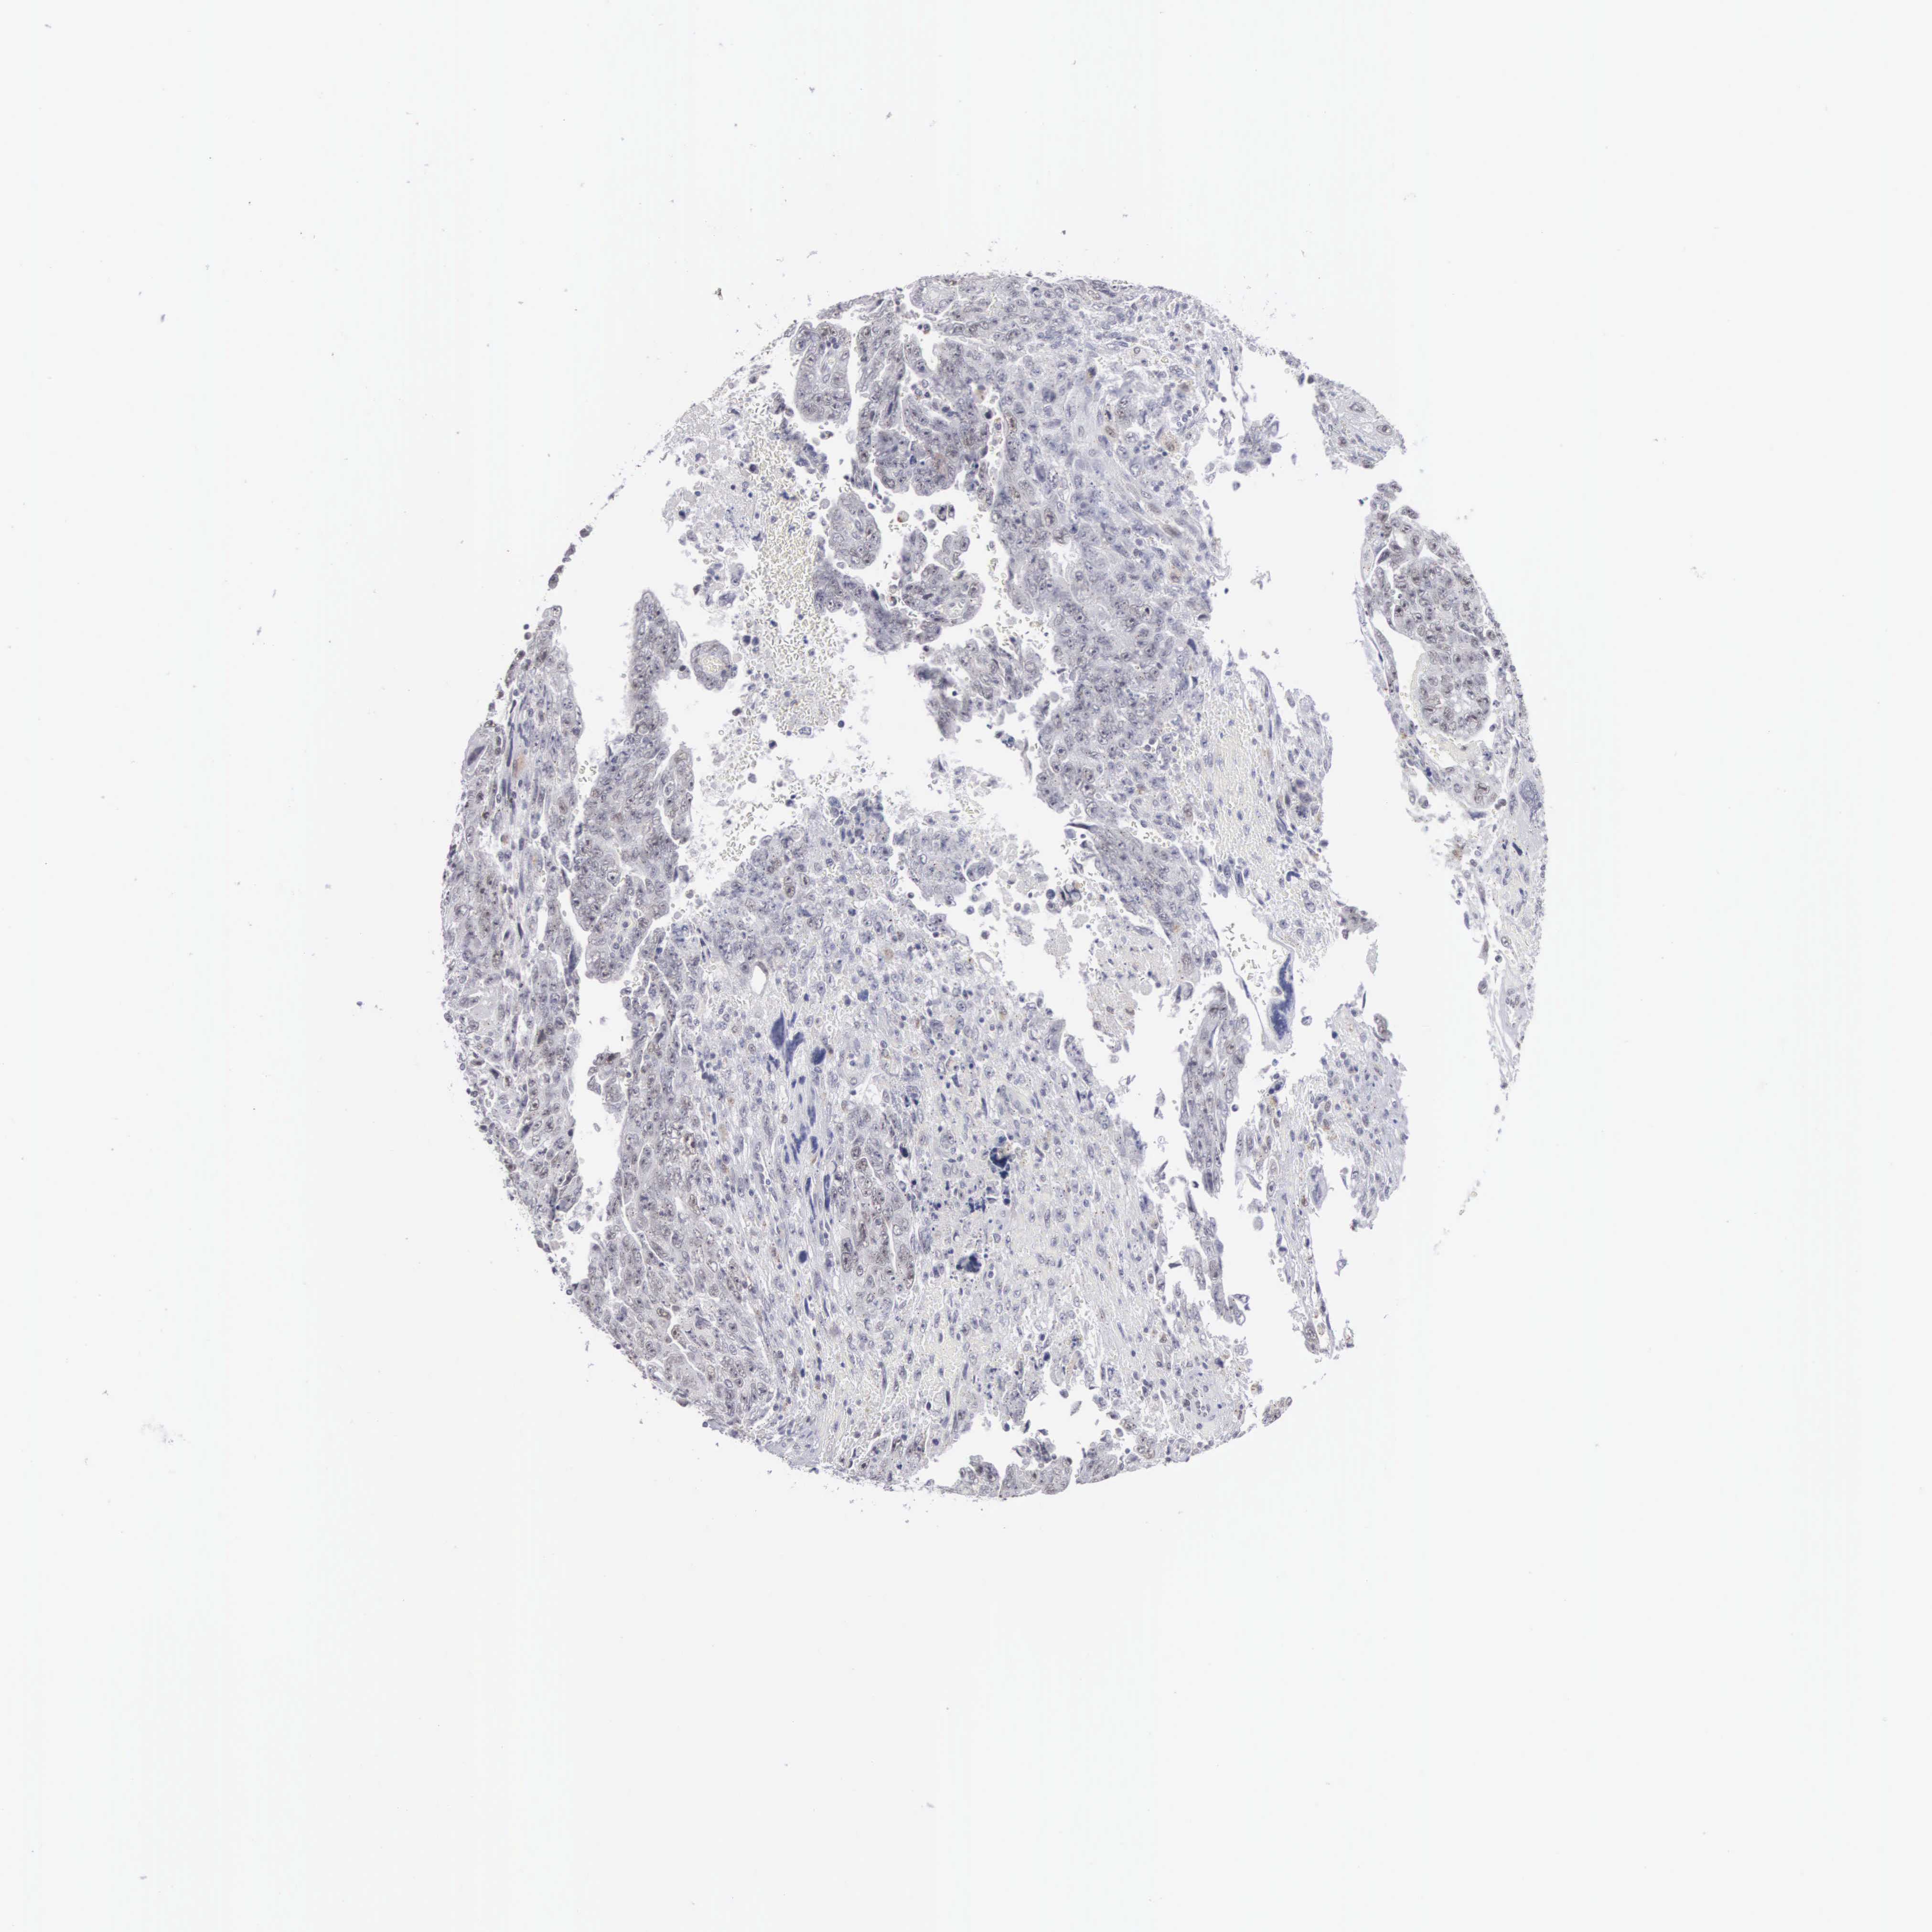

TESTIS CANCER - Protein expressioni

A mouse-over function shows sample information and annotation data. Click on an image to view it in a full screen mode. Samples can be filtered based on level of antibody staining by selecting one or several of the following categories: high, medium, low and not detected. The assay and annotation is described here.

Note that samples used for immunohistochemistry by the Human Protein Atlas do not correspond to samples in the TCGA dataset.

Antibody stainingi

Antibody staining in the annotated cell types in the current human tissue is reported as not detected, low, medium, or high, based on conventional immunohistochemistry profiling in selected tissues. This score is based on the combination of the staining intensity and fraction of stained cells.

Each image is clickable and will lead to virtual microscopy that enables deeper exploration of all samples and also displays staining intensity scores, fraction scores and subcellular localization as well as patient and tissue information for each sample.

Antibody HPA000701

Antibody CAB004495

Staining

High

Medium

Low

Not detected

Intensity

Strong

Moderate

Weak

Negative

Quantity

>75%

75%-25%

<25%

None

Location

Nuclear

Cytoplasmic/membranous

Cytoplasmic/membranous,nuclear

Seminoma, NOS

Carcinoma, Embryonal, NOS